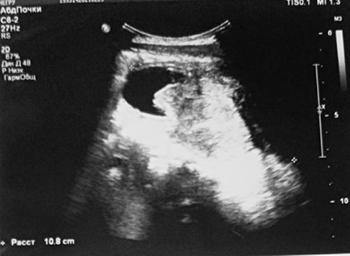

МРТ таза: новообразование больших размеров. МР-картина больше в пользу рабдомиосаркомы, исходящей из предстательной железы с инвазией мочевого пузыря.

Вторичный двусторонний уретерогидронефроз. Состояние после цистостомии (см. рис. 3).

Рисунок 3. Результаты МРТ таза.